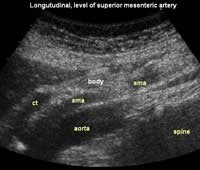

The following study describes anatomical landmarks in the ordinary pancreas of a thin patient:

Transverse planes in caudal direction:

Longitudinal planes from right to left: